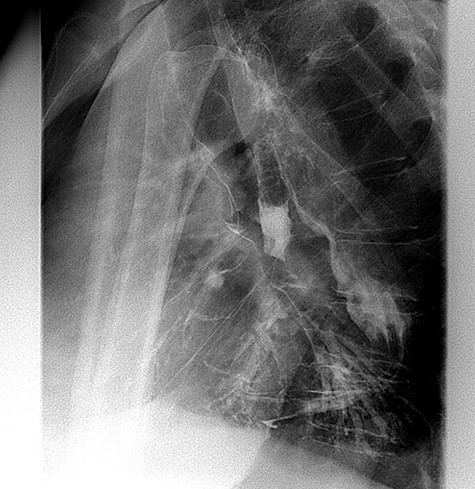

A 49-year-old male, with past medical history of tobacco smoking, who was diagnosed with adenocarcinoma of gastroesophageal junction underwent minimally invasive two-stage oesophagectomy. A month following discharge, he presented with complains of chest pain and persistent coughing (Ohno’s sign); barium swallow examination was conducted. This demonstrated a gastrobronchial fistula, between the newly formed gastric conduit and the left main bronchus (Figures 1 and 2). On endoscopic evaluation, a 5 mm communication between the tip of the gastric conduit and the left main bronchus with no evidence of ischemia and well-vascularised edges was noted.

Barium swallow demonstrating the gastric conduit (white arrow) and left bronchial tree (black arrow).

Lateral view of barium swallow demonstrating gastrobronchial fistula.